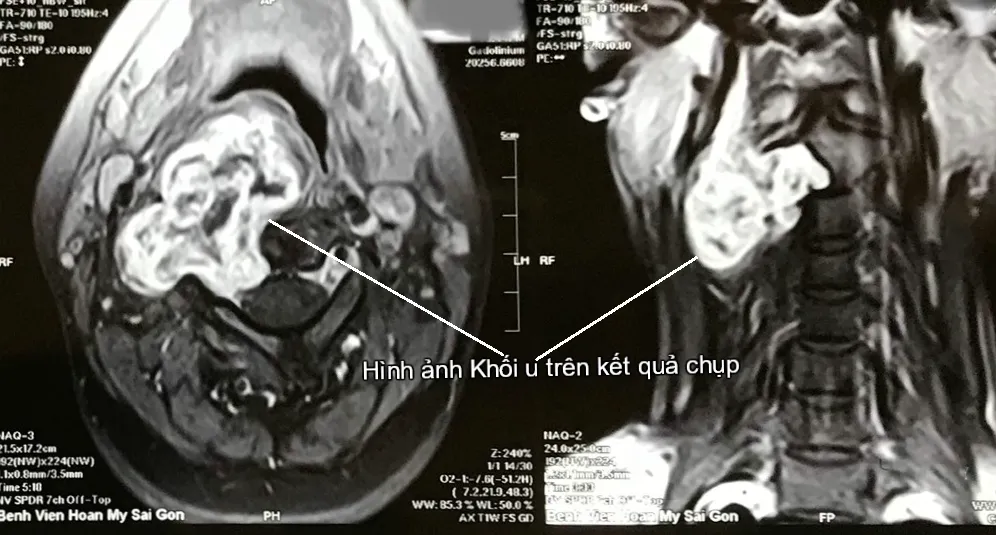

Tại đây, các bác sĩ đã chụp MRI và cho kết quả khối u của chị là u bao dây thần kinh C2-C3 bên phải, xâm lấn thành họng bên phải. Lúc này, khối u có đường kính 6 cm.

Hình ảnh khối u trên kết quả chụp. Ảnh: BV

Khối u có vỏ bao rõ ràng, hình cầu hoặc hình bầu dục, mật độ thay đổi dạng nang mềm hoặc cứng chắc.

Điều trị khối u bao dây thần kinh chủ yếu là phẫu thuật, tiên lượng sau mổ tốt là do các khối u này thường có lớp vỏ bao rõ ràng. Tuy nhiên, vị trí khối u lại thường ở sâu, sát nền sọ, sát với các mạch máu lớn và thần kinh khác nên việc chọn đường vào khối u phải rất cẩn thận.